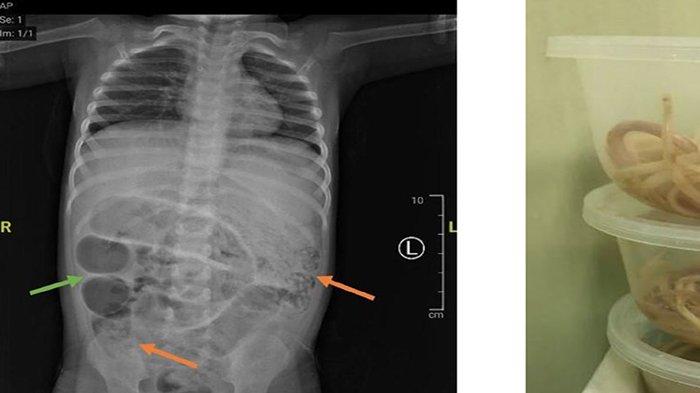

Viral postingan kondisi perut seorang dipenuhi cacing di usus hingga membesar dan tak bisa BAB banyak mendapat sorotan.

TRIBUNPONTIANAK.CO.ID - Viral postingan kondisi perut seorang dipenuhi cacing di usus hingga membesar dan tak bisa BAB banyak mendapat sorotan.

Perut seorang anak laki-laki berusia 3 tahun di Kabupaten Jember, Jawa Timur membesar hingga tidak bisa buang air besar (BAB) selama seminggu.

Bahkan, anak tersebut juga mengalami sakit perut, kesulitan bernapas, dan muntah.

Rupanya, usus anak tersebut penuh cacing.

Dokter di rumah sakit menduga hal tersebut terjadi karena ada sumbatan pada ususnya sehingga tidak berfungsi maksimal.

“Kemudian diperiksa CT scan, memang menggambarkan suatu kondisi yang disebut ileus obstruktif, yaitu buntunya saluran pencernaan akibat sesuatu,” ucap dia.

Setelah dioperasi, ternyata ada tiga titik sumbatan yang ditemukan oleh dokter dalam usus anak tersebut.